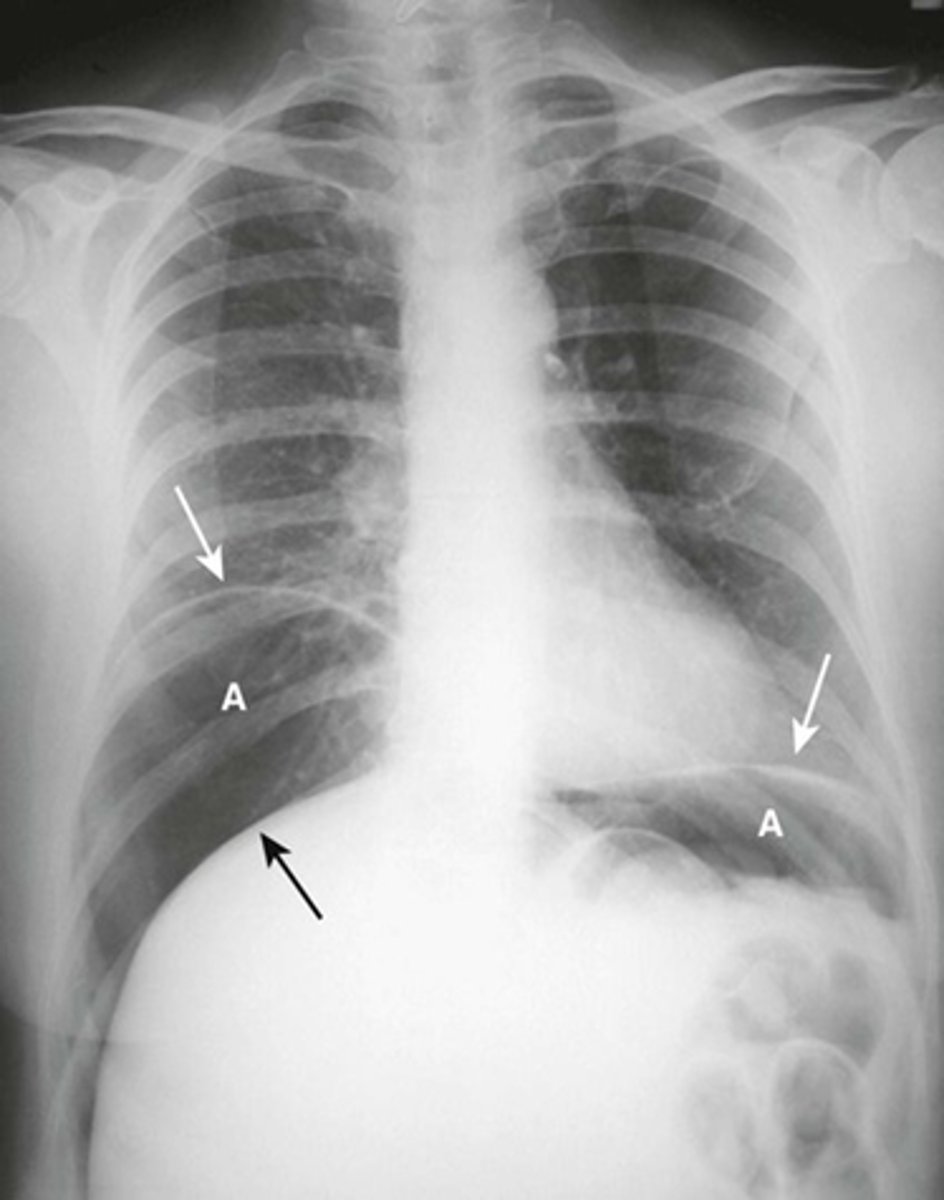

A:

WHITE ARROWS: soft tissue mass on LUQ

BLACK ARROW: displacement of bowels to the right

B: CT of the same patient

WHITE ARROW: large renal cyst arising from left kidney, displacing it and surrounding bowel.

BLACK ARROW: left kidney.

S: spleen, compressed by cyst.